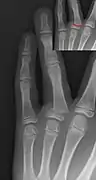

- Salter–Harris III fracture of big toe proximal phalanx.

- Salter–Harris IV fracture of big toe proximal phalanx.